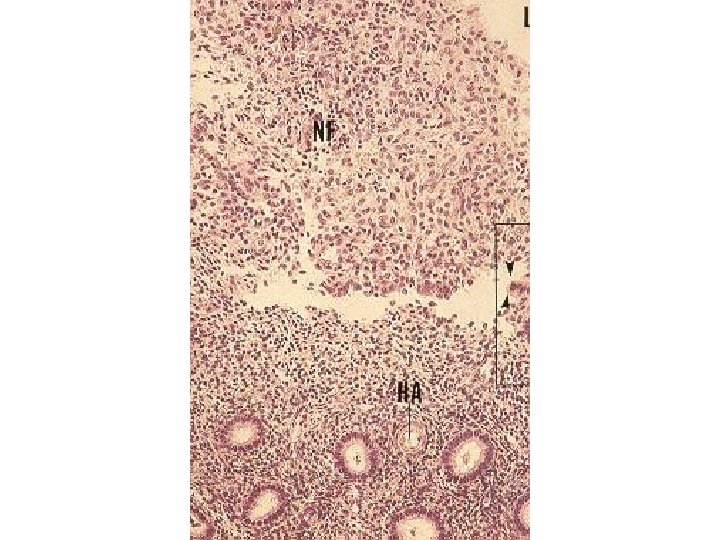

Endometrium áEndometrium is mucosal lining of uterus composed of a simple columnar epithelium áEpithelium has ciliated columnar cells and secretory columnar cells áLamina propria composed of dense irregular connective tissue and vessels supports epithelium and houses simple tubular glands áThe glands have not ciliated cells áEndometrium has 2 zones w. Functional layer w. Basal layer

Endometrial Layers Functional layer is a thick superficial layer sloughed off during menstruation and replaced during each menstrual cycle Functional layer vascularized by coiled helical arteries that originate from arcuate arteries in stratum vasculare Basal layer is a deep narrow layer retained after menstruation whose glands epithelium and connective tissue element regenerate functional layer Basal layer supplied by short straight arteries which originate from arcuate arteries in stratum vasculare

Proliferative (Follicular) Phase ÷ Days 5 -14 leading up to ovulation ÷ Estrogen produced by theca cells of ovarian follicle ÷ Cells of gland bases proliferate forming simple columnar epithelium and tubular glands of endometrium ÷ Connective tissue cells proliferate in lamina propria ÷ Coiled arteries grow into regenerated lamina propria ÷ Functionalis of endometrium become 2 -3 mm in thickness ÷ glands have a straight tubes with narrow lumens but their cells accumulate glycogen ÷ At the day 14 the functional layer has been fully restored

Secretory (Luteal) Phase í Begins after ovulation, days 15 -28 í Corpus luteum forms and produces progesterone í Glands develop further, become highly coiled, branched and begin to secrete í Coiled arteries also attain full development í Endometrium reaches 5 mm in thickness due to edema and accumulated glycogen secretions of the glands